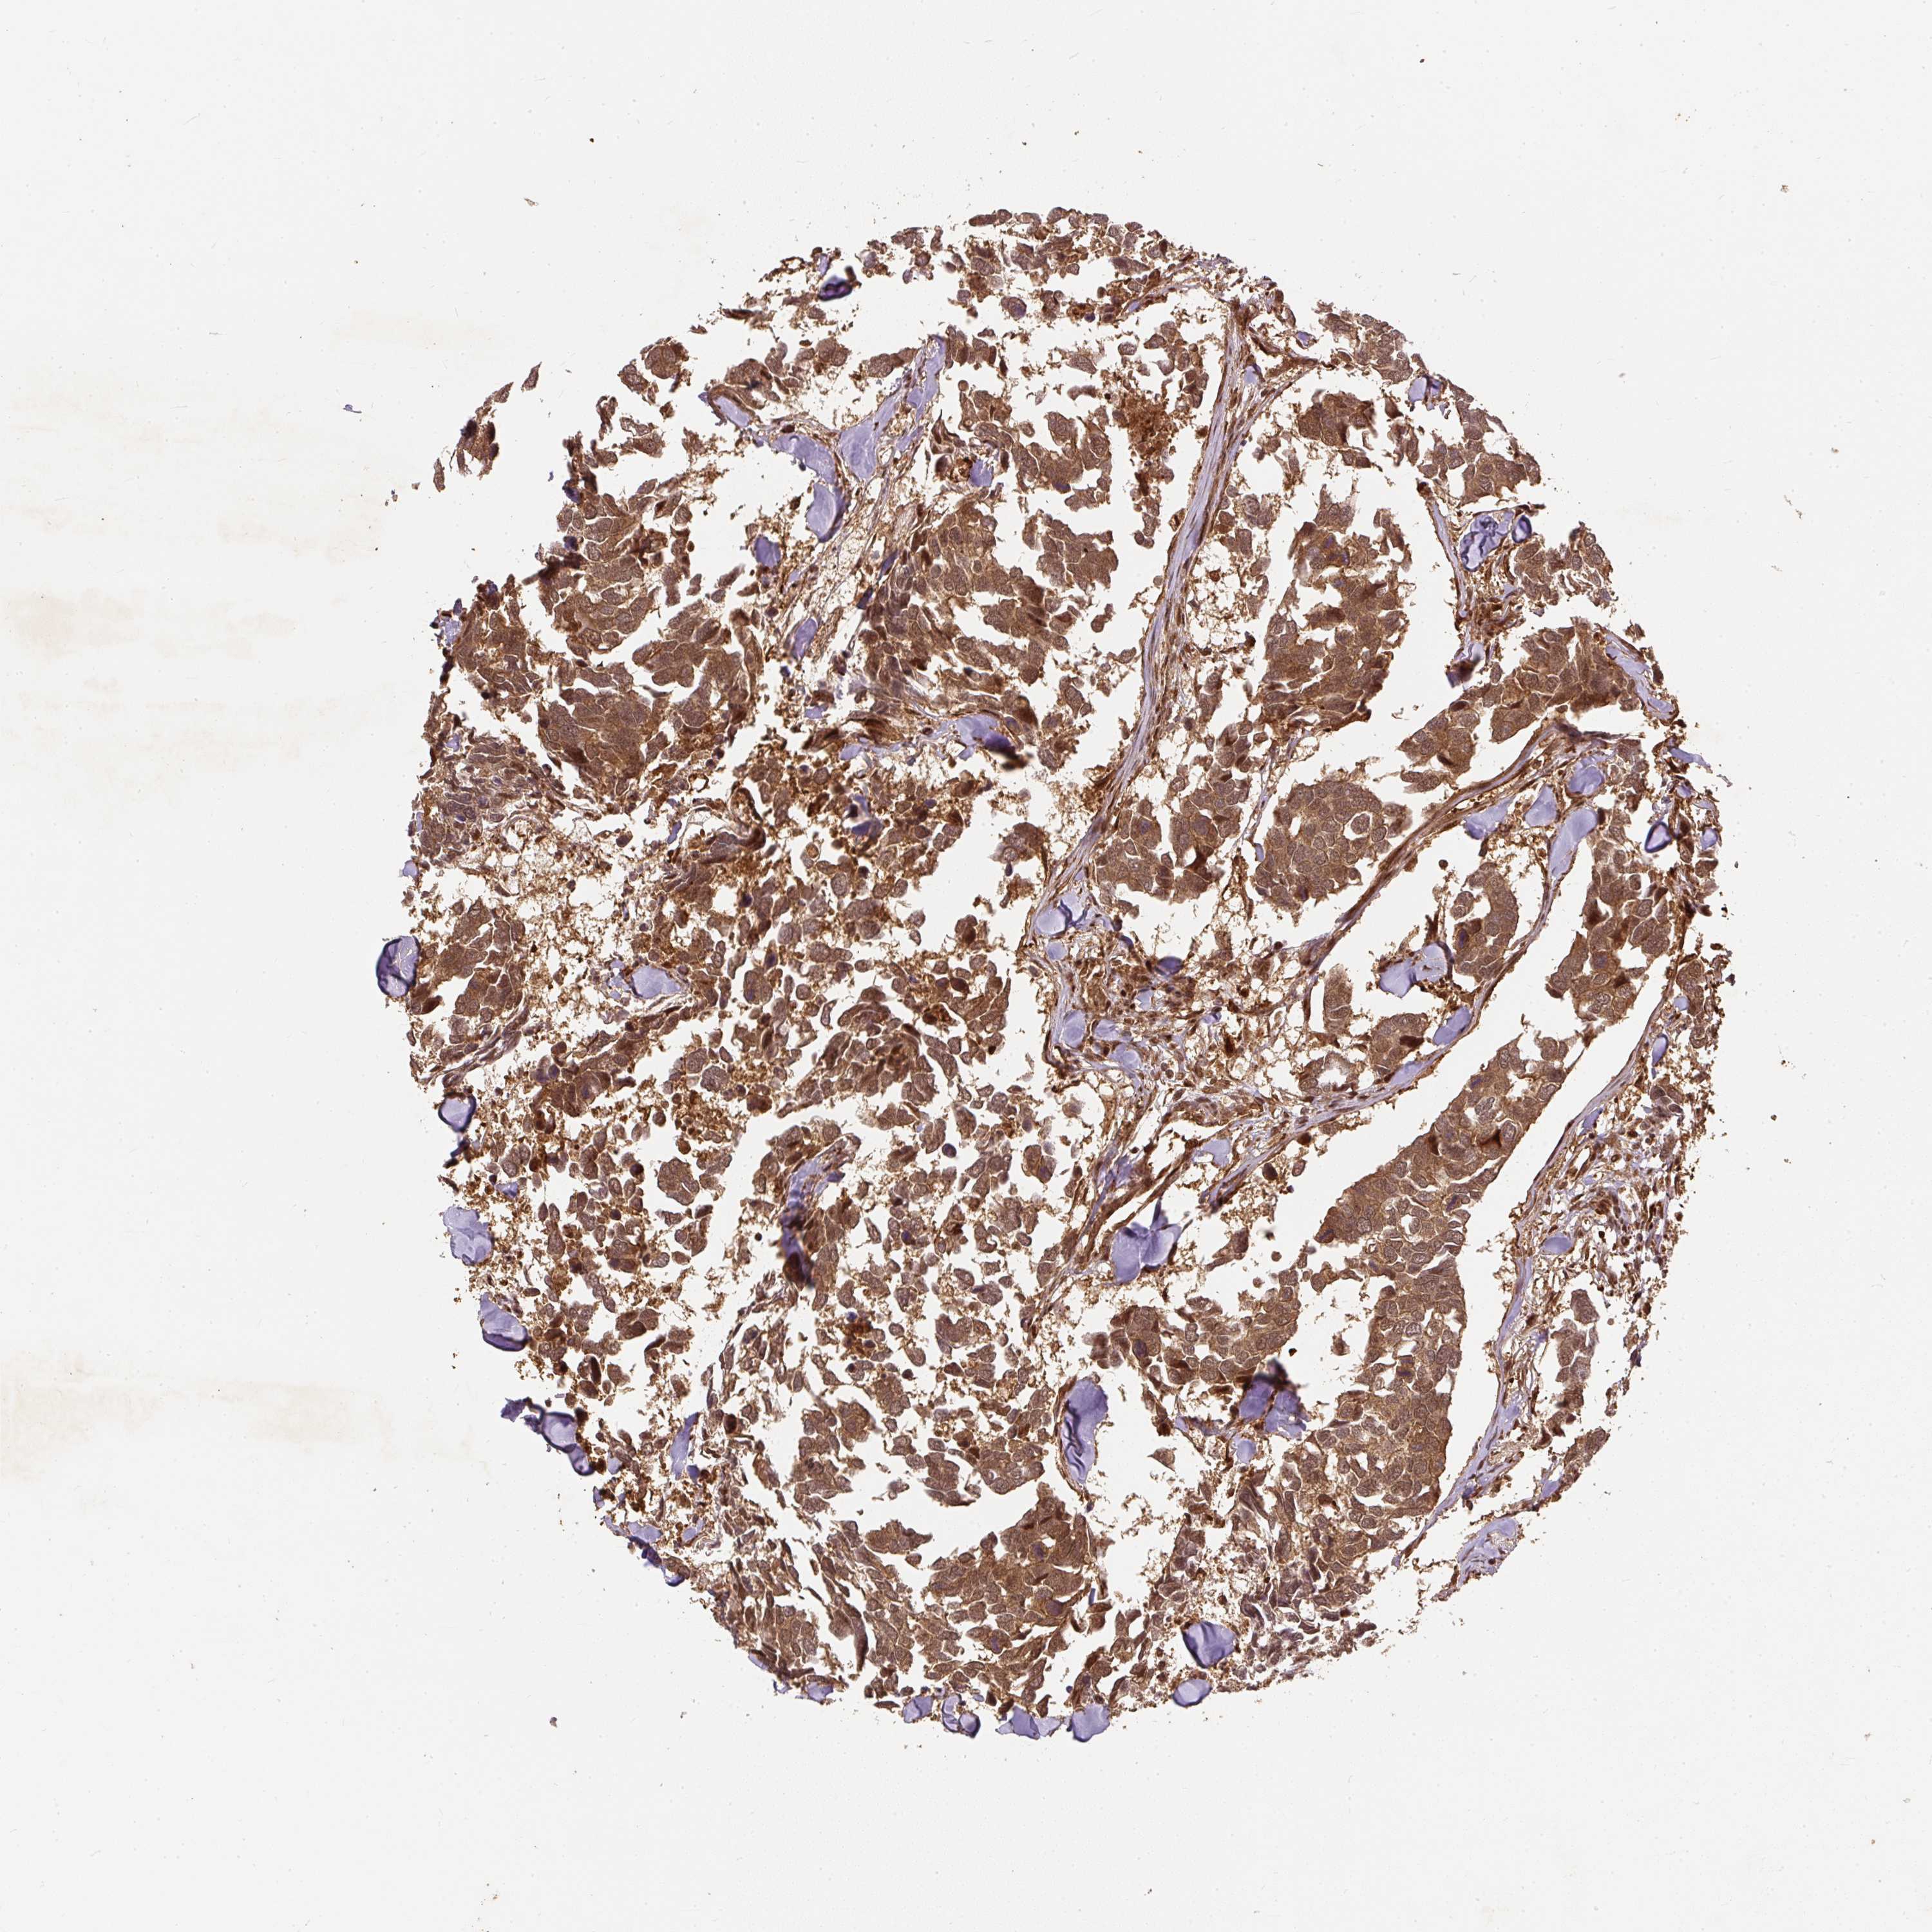

CANCER BREAST CANCER Show tissue menu

BRCA TCGA BRCA VALIDATION PROTEIN EXPRESSION